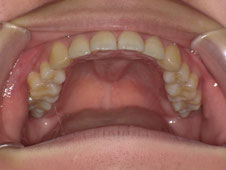

まったくない方もおられますが、写真のように歯の下の左右にあるコブみたいなものを「骨隆起」といいます。上顎にも真ん中に同じようにできます。

自覚がない方も多いので、ぜひご自身のお口の中を鏡で観察してみてください。

子どもの頃にはなかったのに、なぜこんなに骨がモコモコ盛り上がってくるのかというと、実は、噛む力が強かったり食いしばりや歯ぎしりなどが原因なのです。

骨隆起がある=食いしばる力で歯を壊してしまうリスクが高いということになるので、その食いしばりへの対策が必要です。定期検診など診療の際にお話していますので、参考にしていただければと思います。

なお、この骨隆起自体は、骨の上に被っている粘膜が薄く傷付きやすかったり歯型採りや入れ歯を入れた際に当たって痛いというデメリットがありますが、特に治療の必要はありません。